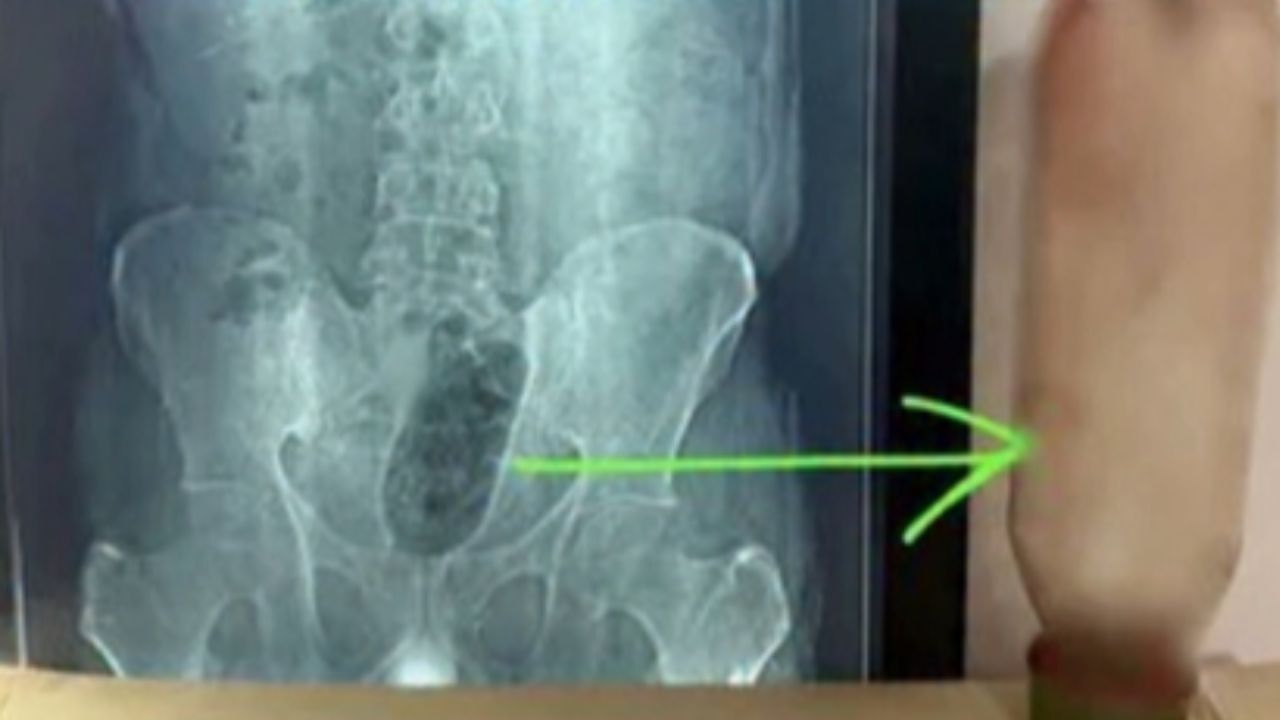

यह अजीबोगरीब मामला आगरा की साकेत कॉलोनी स्थित नवदीप हॉस्पिटल में सामने आया. मंगलवार को 38 वर्षीय विवाहित युवक को तेज दर्द की शिकायत के साथ अस्पताल लाया गया. डॉक्टरों ने जब उसका एक्स-रे किया तो मलाशय के अंदर एक 1 लीटर की पानी की बोतल फंसी हुई दिखाई दी. मरीज ने डॉक्टरों को बताया कि बोतल करीब 36 घंटे से उसके शरीर के अंदर फंसी हुई है, जिसके कारण उसे असहनीय दर्द हो रहा था.

अस्पताल के निदेशक और वरिष्ठ सर्जन डॉ. सुनील शर्मा के अनुसार मरीज की हालत देखते हुए तुरंत इमरजेंसी सर्जरी का फैसला लिया गया. डॉक्टरों के लिए यह ऑपरेशन काफी चुनौतीपूर्ण था, क्योंकि बोतल निकालते समय मलाशय के फटने या गंभीर चोट लगने का खतरा बना हुआ था. करीब 1 घंटे 10 मिनट तक चली सर्जरी के बाद डॉक्टरों की टीम ने बेहद सावधानी के साथ बोतल को बाहर निकाल लिया.